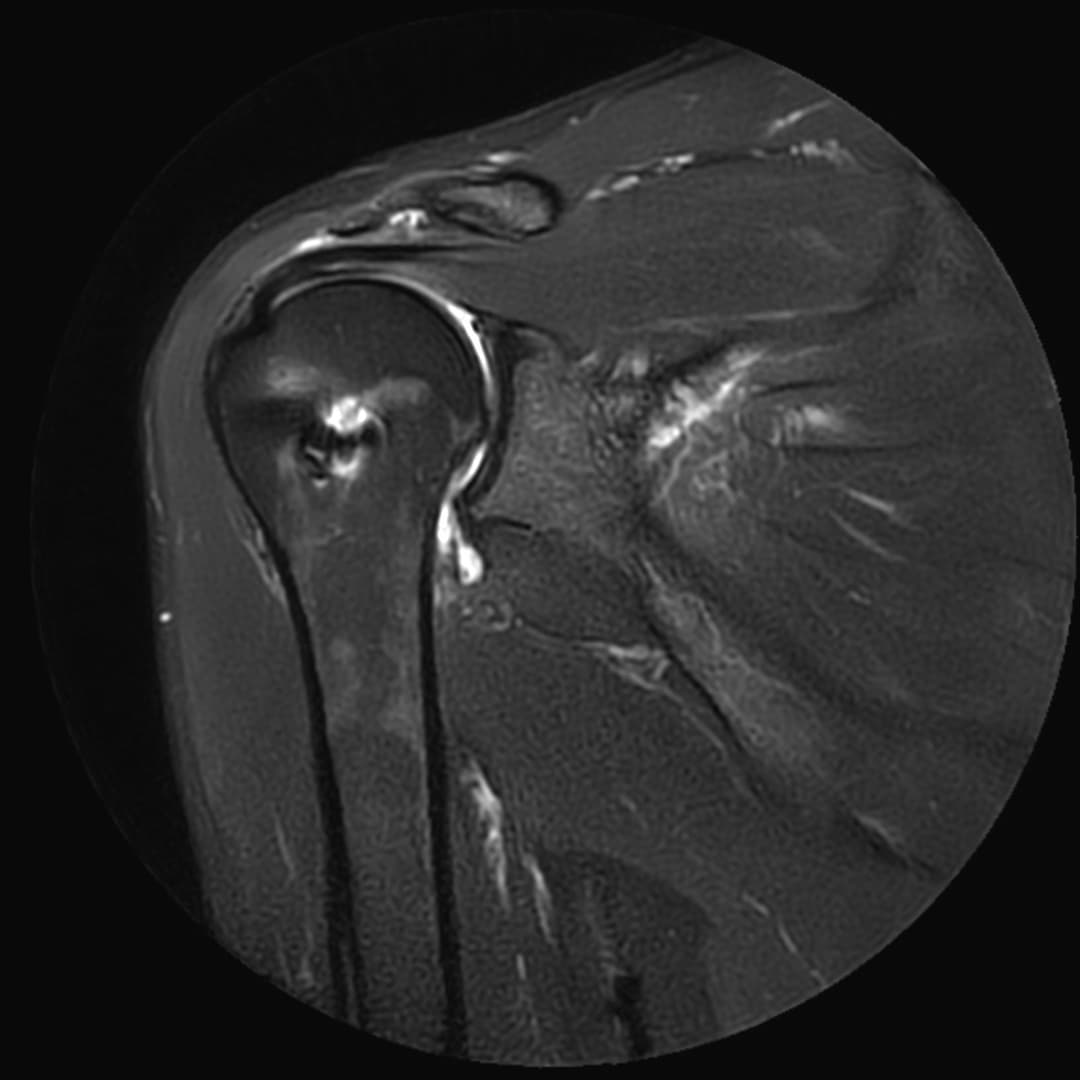

Rupture du tendon sous-scapulaire

IRM

Ténodèse du long biceps intacte. Tendons sus et sous épineux respectés. Large diffusion du contraste depuis compartiment articulaire vers la BSAD.

Rupture du tendon sous-scapulaire avec rétraction grade II-III